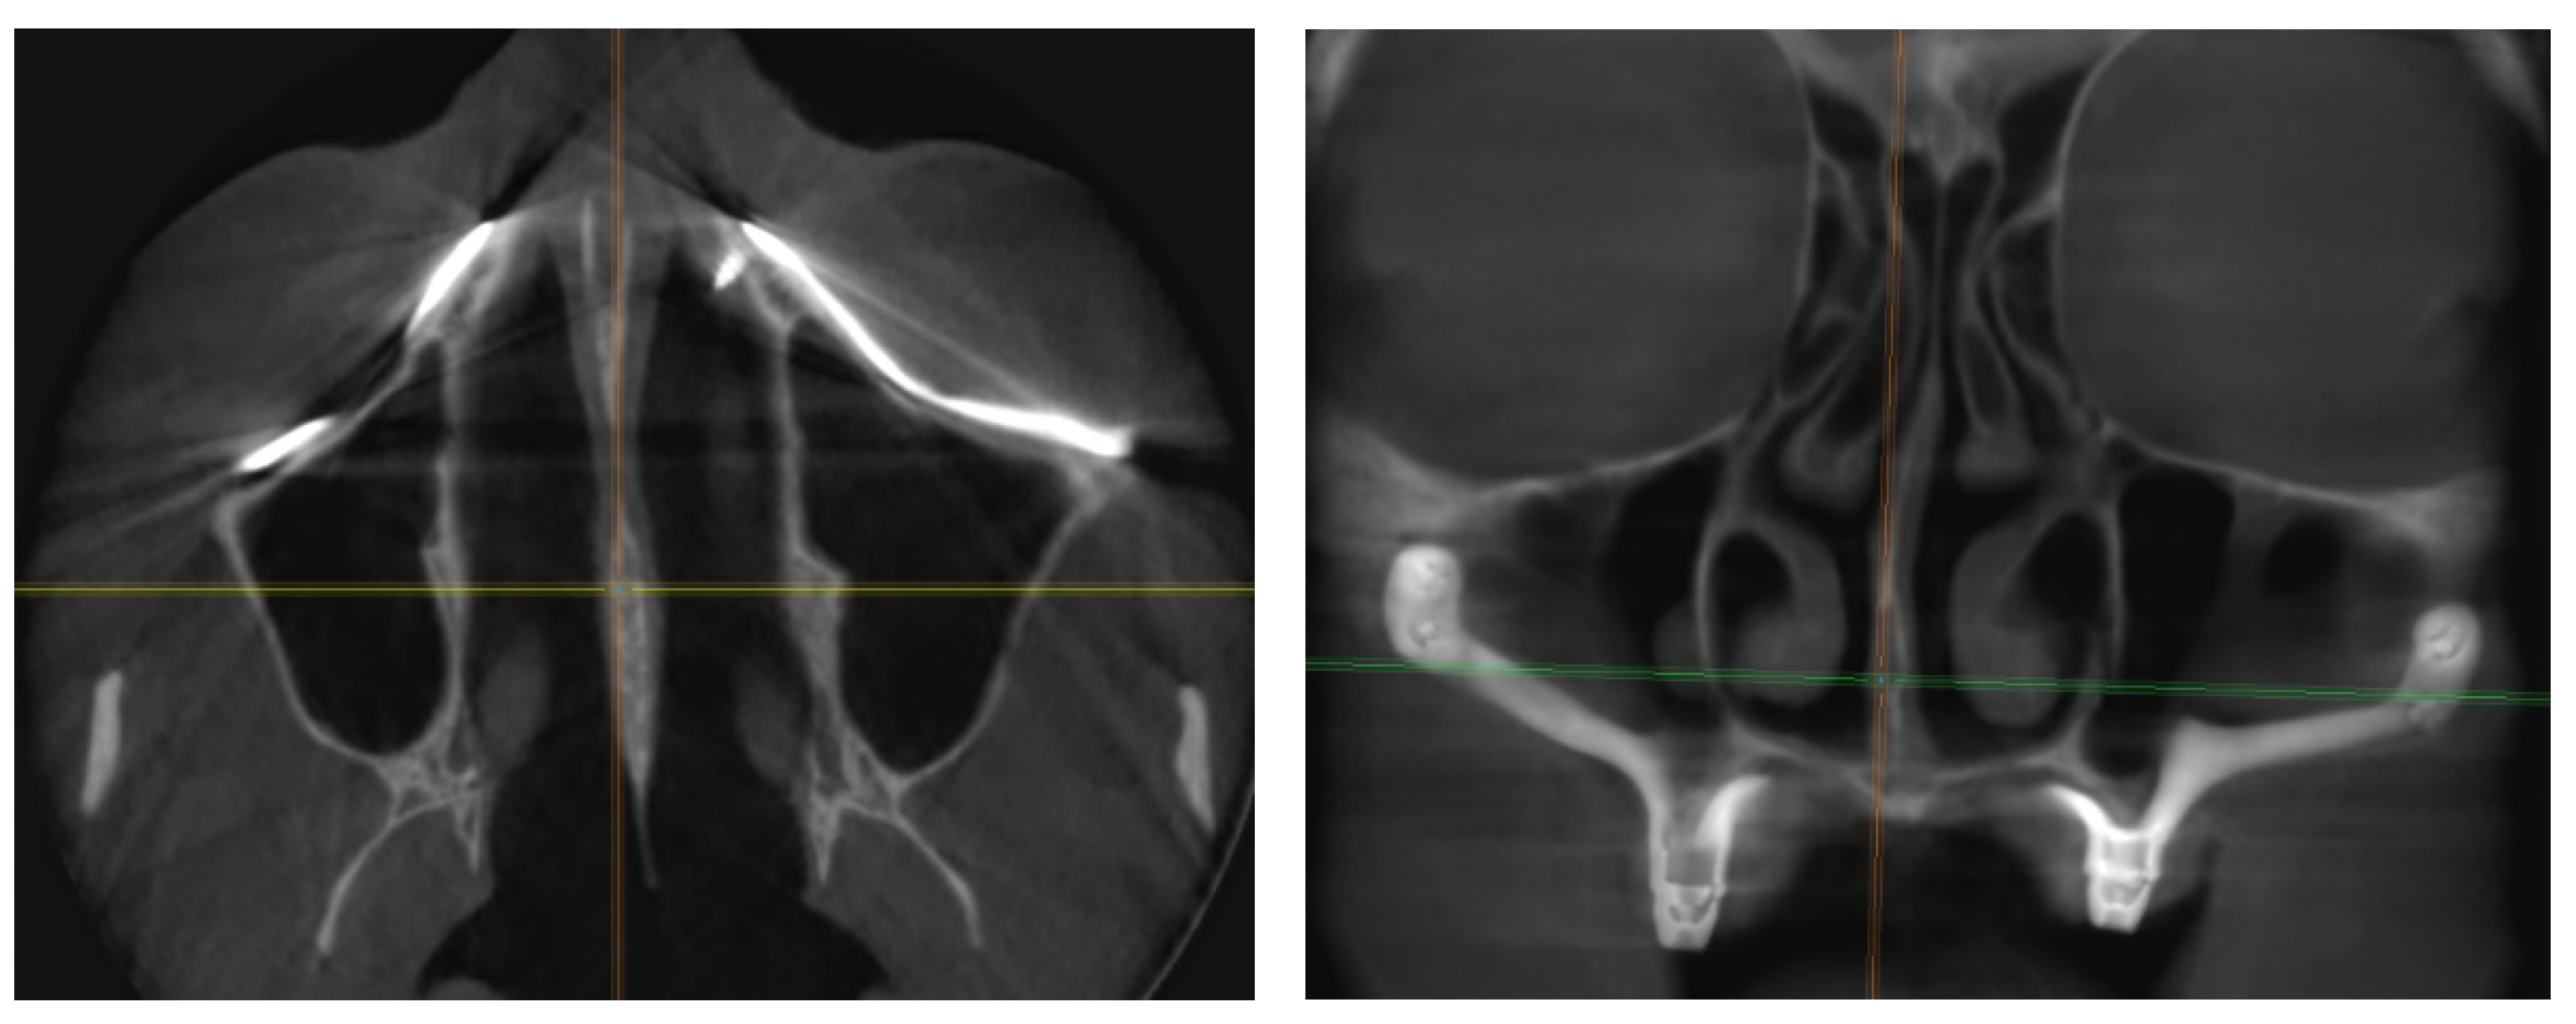

2.2. Pre-Surgical Cone-Beam Computed Tomography (CBCT)

2.3. Design and Production of Patient-Specific Subperiostal Implants